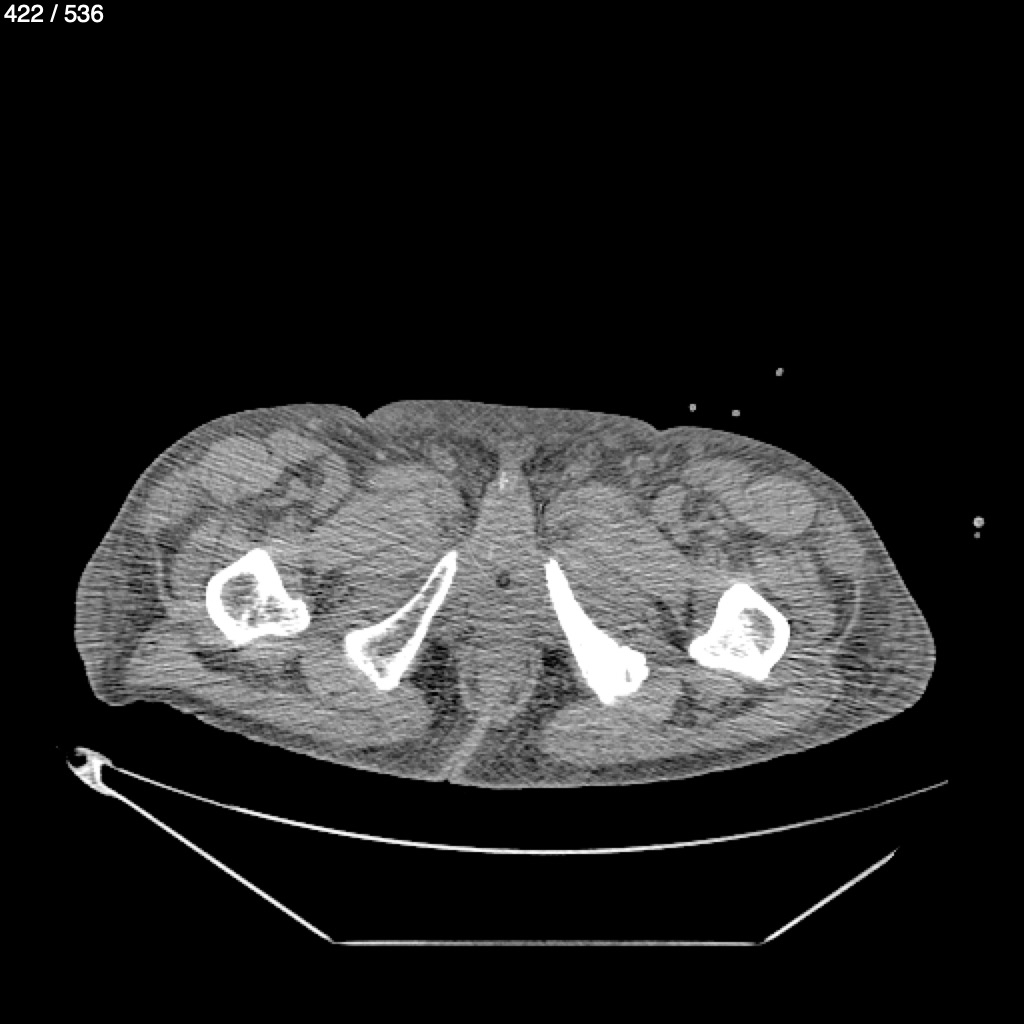

Angel Villalobos Palomeque 73 A - T.C Abdomen Simple